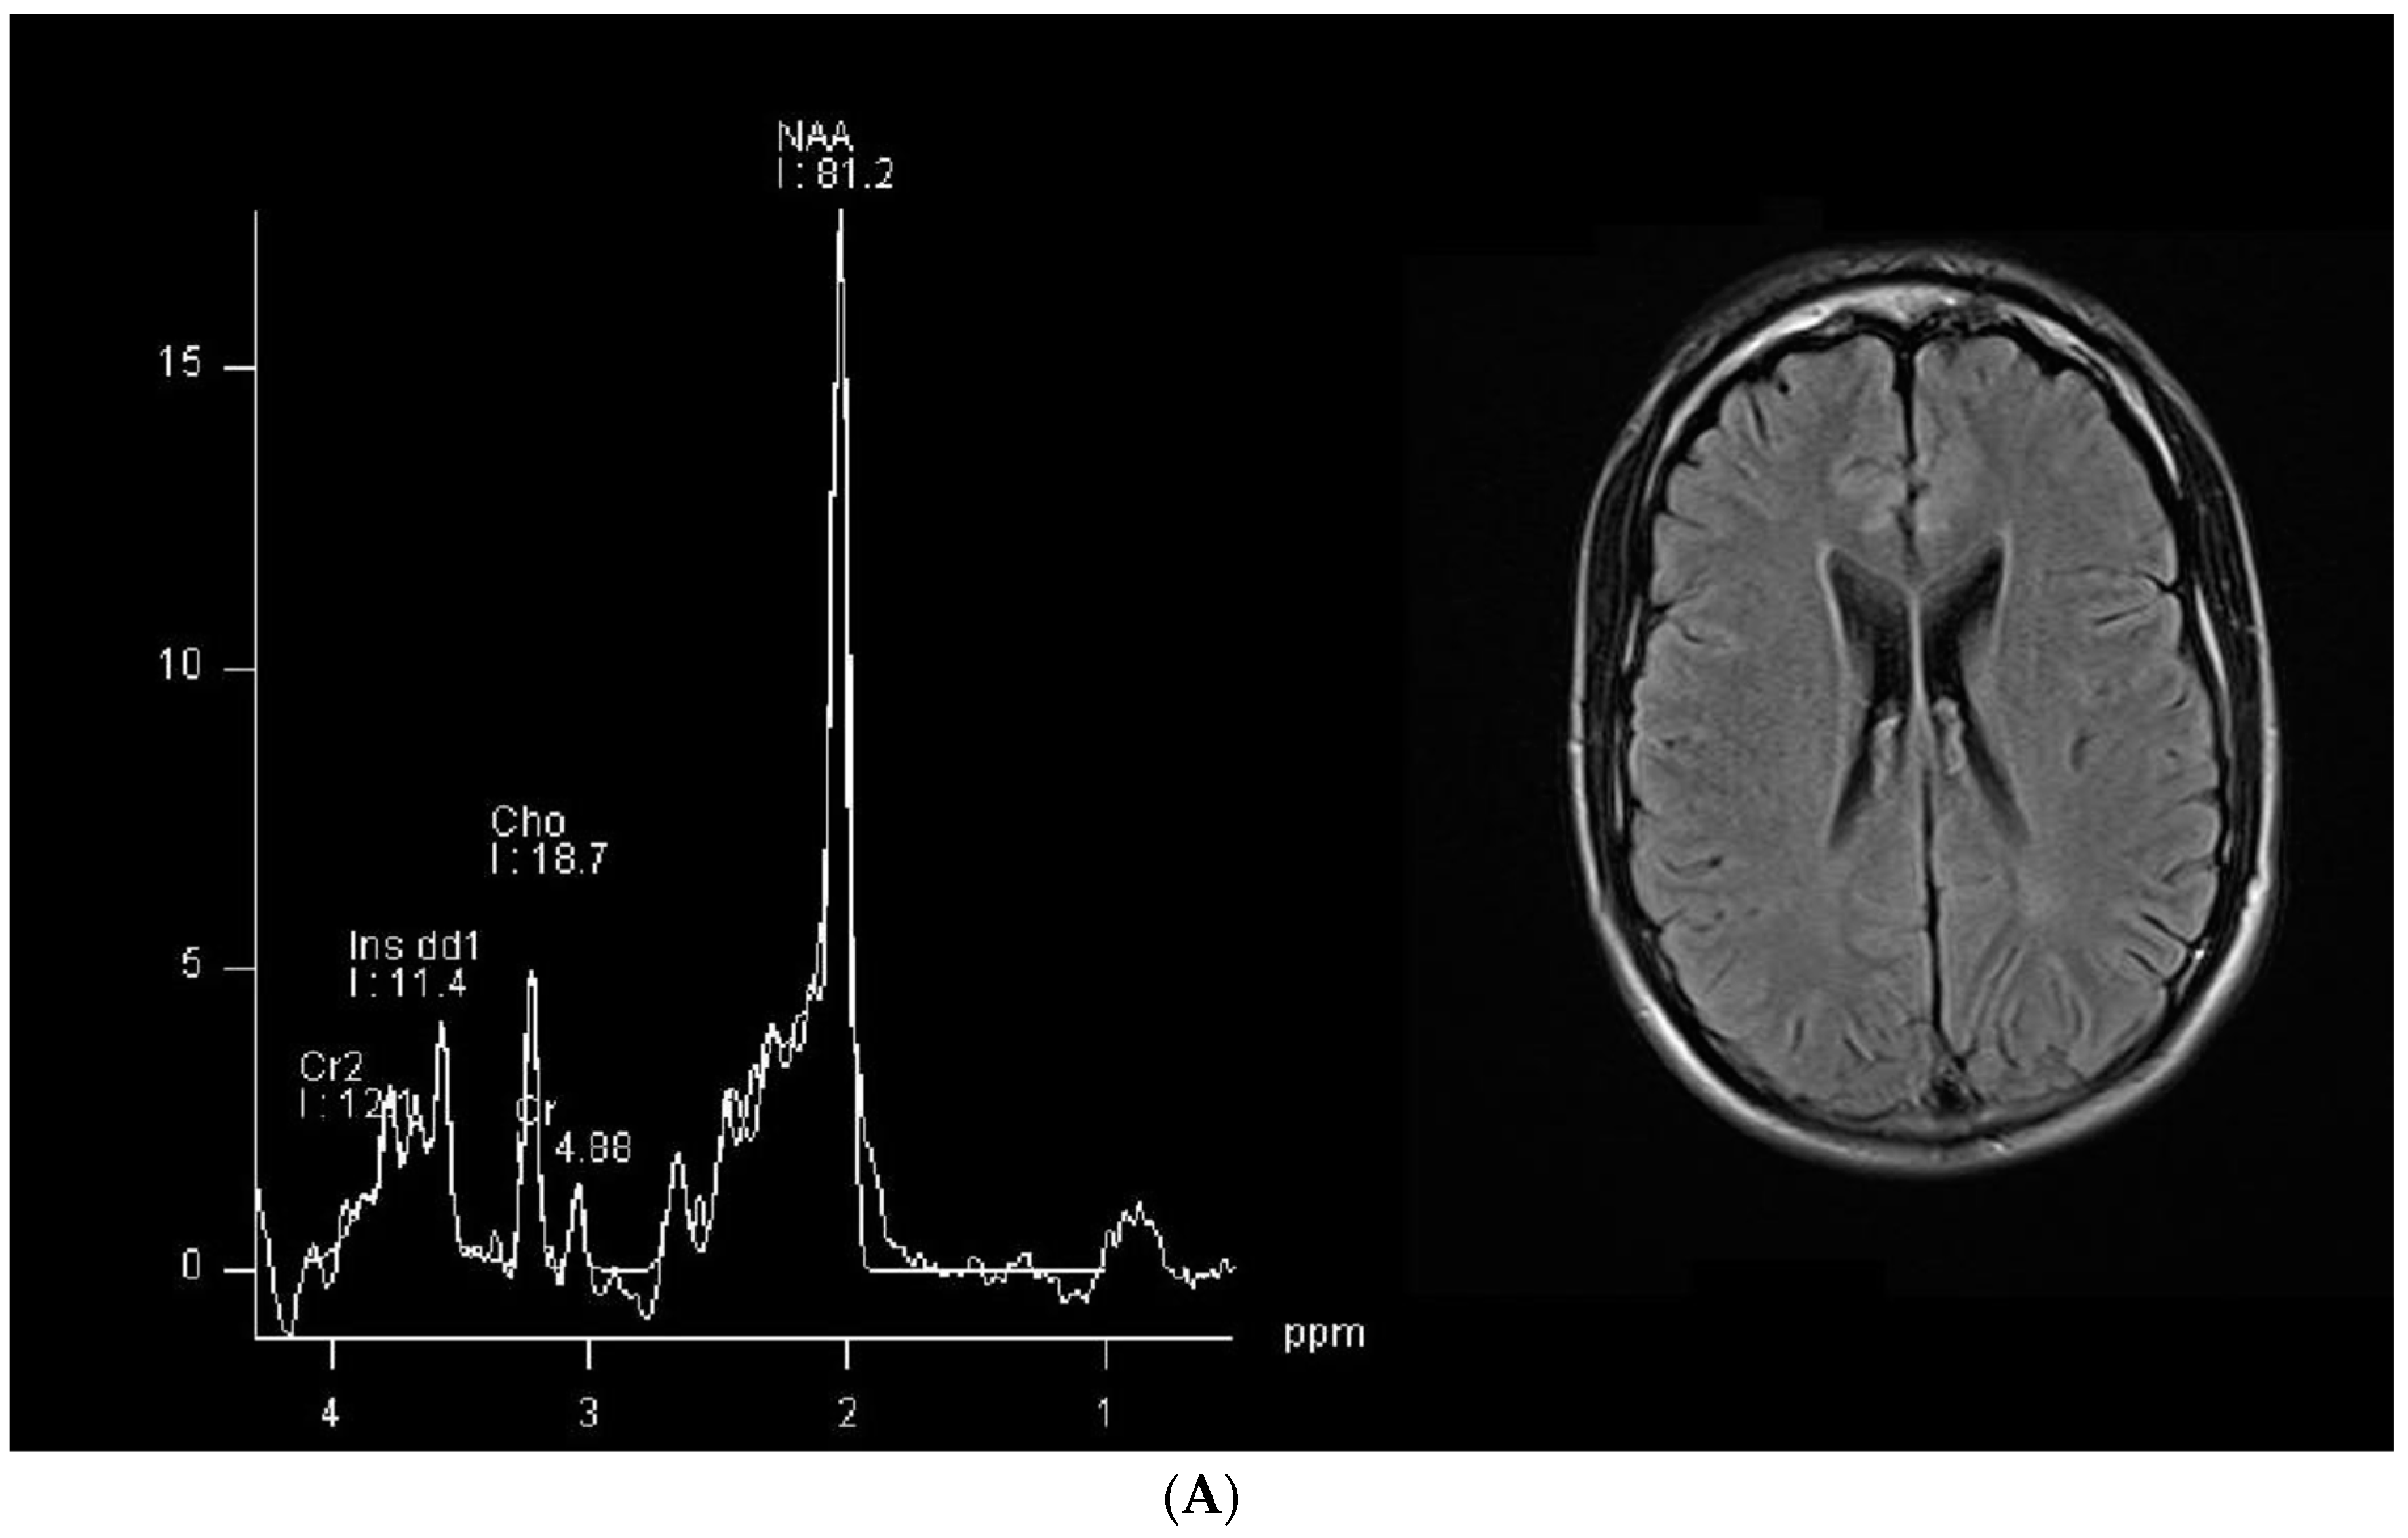

| Age | 28 years old | 18 years old |

| Speech | He only speaks a few words with semantic meanings; verbal understanding is spared. | Some difficulty in finding words but information is conveyed and his vocabulary has a fair amount of complexity. |

| Cognitive state | Severe cognitive impairment, lack of attention with only occasional collaboration; he is often agitated, especially in unfamiliar situations. | Cognitive impairment but he shows a fair amount of attention and concentration; behavior is not grossly abnormal. |

| Seizures | Seizures in the past, not in the past two years. | Seizures up to the age of 6, but no seizures since then. |

| Neurological examination | No focal lesion signs, global motor impairment, fatuity, hyperkinesia, mild axial hypotonia, internal rotation of the feet. Right hand dominance. | Normal neurological examination except for slight impairment in fine motor movements of the hand fingers, bilaterally. Right hand dominance. |